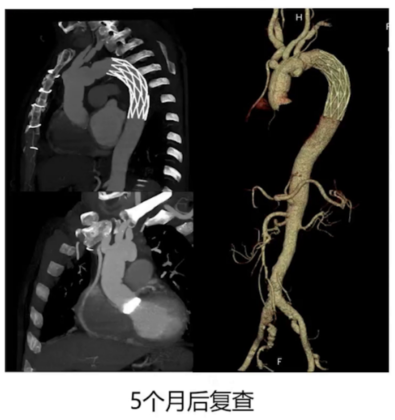

患者急诊行外科手术治疗(Bentall术+主动脉弓人工血管置换+支架置入及冠状动脉旁路移植术)。术后5个月复查,人工瓣膜、血管及吻合口未见异常,冠状动脉支架在位,恢复良好。